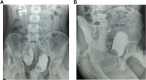

One of the most challenging aspects of urology is restoring patency to ureters with long defects. In certain cases, it may not be feasible to perform plastic surgery on the ureter with its own tissue or bladder. In such instances, alternative solution like appendicular ureteroplasty may be promising solution. Ureteral injuries have several etiologies, some of them are secondary to unintentional ureteral trauma during surgery. More than half of these injuries are unrecognized during the first laparotomy. Extensive ureteral injuries are difficult to repair, even with application of several types of surgical techniques. The advantage of appendicular ureteroplasty is the simplicity of the ureteral replacement technique without compromising other substitution options in case of failure. This is a case report of a young adult with abdominal gunshot injuries, with significant loss of tissues located to distal third of the right ureter. The appendicular urethroplasty was successfully performed. The patient remained stable after one year of out follow-up as an outpatient.